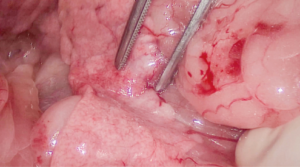

Se realizó una laparotomía exploratoria por línea media ventral y se observó un nódulo en el cuerpo del páncreas con invasión de un trombo tumoral en la vena porta y otro nódulo de menor tamaño en el lóbulo izquierdo (imágenes 2A y 2B).

Se realizó la disección del lóbulo izquierdo y el cuerpo del páncreas, usando un sellador vascular/tisular, hasta una porción macroscópicamente libre de lesión. Se continuó con la disección de la vena porta y la vena gastroduodenal. A continuación, se colocaron tres torniquetes de Rummel (en la vena porta craneal y caudal a la invasión y en la vena gastroduodenal) y se procedió a realizar la venotomía de la vena porta y ligadura completa de la vena gastroduodenal al estar en la zona de la venotomía. De esta manera, se liberaron la porción del páncreas diseccionada y el trombo tumoral que invadía la vena porta. El cierre venoso se efectuó con sutura continua con polipropileno 6/0 USP y con hemoclips; después, se colocó un apósito de colágeno (vídeo 2).